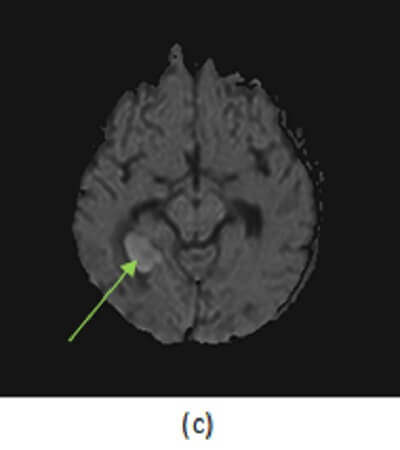

Figure 1: (a) right medial temporal lobe mass has high T2 signal centrally (red arrow) and a low T2 rim (purple arrow). There is surrounding vasogenic edema (brown arrow). (b, blue arrow) T1 post contrast demonstrates thick walled rim enhancement . There is also central restricted diffusion (green arrow, ADC not shown but low signal).

Most brain abscesses result from hematological dissemination of infection; as a result, the grey white junction (site of greatest blood flow) is the most common location. Early infection of the brain parenchyma is termed cerebritis and is characterized by a focal infiltration of inflammatory infiltrates, manifested on MRI by T2/FLAIR hyperintensity without restricted diffusion or enhancement. If left untreated, cerebritis may mature into an abscess – a mass with central necrosis contained by a rim of fibroblasts, manifested by central restricted diffusion with an enhancing, sometimes hypointense T2 rim and extensive vasogenic edema. Smaller “daughter” abscesses may also be present. These characteristics, unique to the pathology of abscesses, help distinguish them from other causes of rim enhancing brain masses.